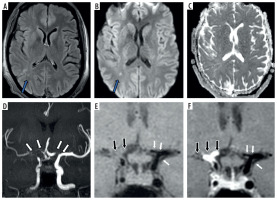

Figure 1

Fourty one-year-old female presenting with young stroke. Axial fluid-attenuated inversion recovery (FLAIR) (A), axial diffusion-weighted imaging (B) and axial view apparent diffusion coefficient map (C) image showing few foci of non-diffusion restricting FLAIR hyperintense signal intensity in right parieto-temporal lobe (white arrows in A and B). Coronal anterior maximum intensity projection time-of-flight magnetic resonance angiography (MRA) image (D) shows stenotic right supraclinoid internal carotid artery (ICA), right middle cerebral artery (MCA) with occluded right terminus ICA and right anterior cerebral artery (ACA) and also stenotic left terminus ICA (white arrows in D). Coronal pre-contrast vessel wall imaging (VWI) (E) and coronal post contrast VWI (F) showing vessel wall thickening (black arrows in E) and grade 2 concentric enhancement of right supraclinoid, terminus ICA, right MCA and ACA (black arrows in F). Grade 1 concentric enhancement also noted in left supraclinoid, terminus ICA and left ACA (white arrows in E and F)